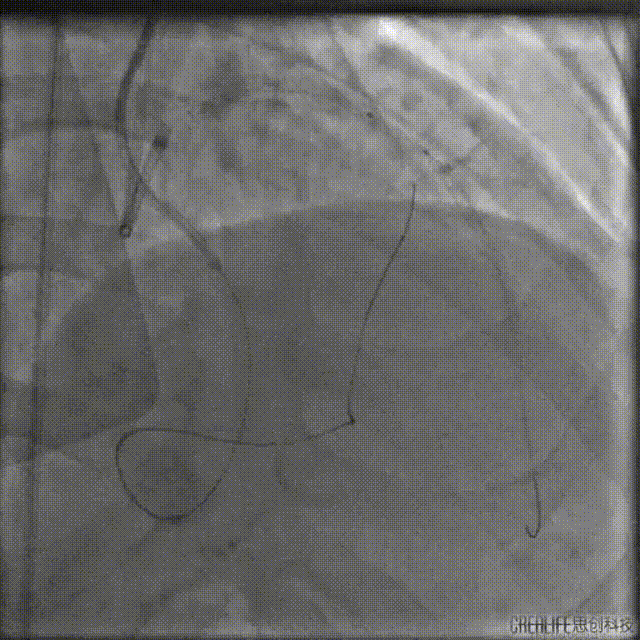

左冠:7Fr EBU3.5;右冠:7Fr AL1.0;Runthrough导丝送至RCA远端,LAD送P200导丝在微导管支撑下进入CTO病变体部。

P200导丝反复调整仍无法突破CTO病变远段,遂走行至D1,通过逆向造影进一步确认。

送入双腔微导管增强支撑,并送入第二根P200导丝继续尝试正向进攻,未能进入LAD中段真腔。

撤出微导管,1.5mm球囊扩张LAD近段后,送入IVUS导管,明确LAD近段导丝是否走行在真腔内,观察LAD在D1分叉处的开口位置,指导CTO导丝的进攻方向。

回撤显示导丝位于真腔,分叉处CTO入口在11-12点处,遂在X线影像中标记入口位置。

重新送入双腔微导管及P200导丝,在CTO入口处尝试进入远端真腔,但反复调整导丝仍未成功。